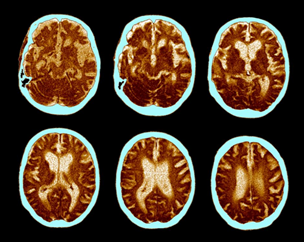

صورة (1): يظهر مسح الدماغ لمرضى ألزهايمر فقدانًا تدريجيًا في خلايا الدماغ، ويحدث ذلك بسبب ترسب بروتين غير طبيعي في الدماغ، والذي بدوره يقتل الخلايا العصبية ويتسبب في ضمور المخ.

SCIENCE PHOTO LIBRARY - ZEPHYR, GETTY

ما السبب في عدم النجاح؟ يوضح ويليامسون: لم يتمكن العلماء بعد من فهم السبب الدقيق لحدوث المرض، على الرغم من البحث العلمي المستمر الذي بدأ منذ اكتشاف المرض في العام (1906). النظرية السائدة تُرجح ترسب بروتين غير طبيعي في الدماغ يتسبب في توقف نشاط الخليّة العصبيّة وضمور أنسجة الدماغ. ولكن، لم يستطع العلماء حتى الآن تفسيرها بسبب ترسّب تلك البروتينات، أو بالضبط ما الدور الذي تلعبه تلك الترسبات في موت الخلايا والذي يؤدي إلى ظهور أعراض مرض ألزهايمر.